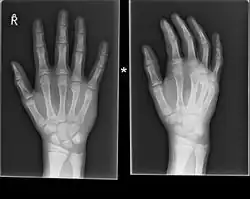

Boxer fracture

Boxer fracture of the 4th and 5th knuckles

Diagnosis by a doctor’s examination is the most common, often confirmed by x-rays. X-ray is used to display the fracture and the angulations of the fracture. A CT scan may be done in very rare cases to provide a more detailed picture.[8]